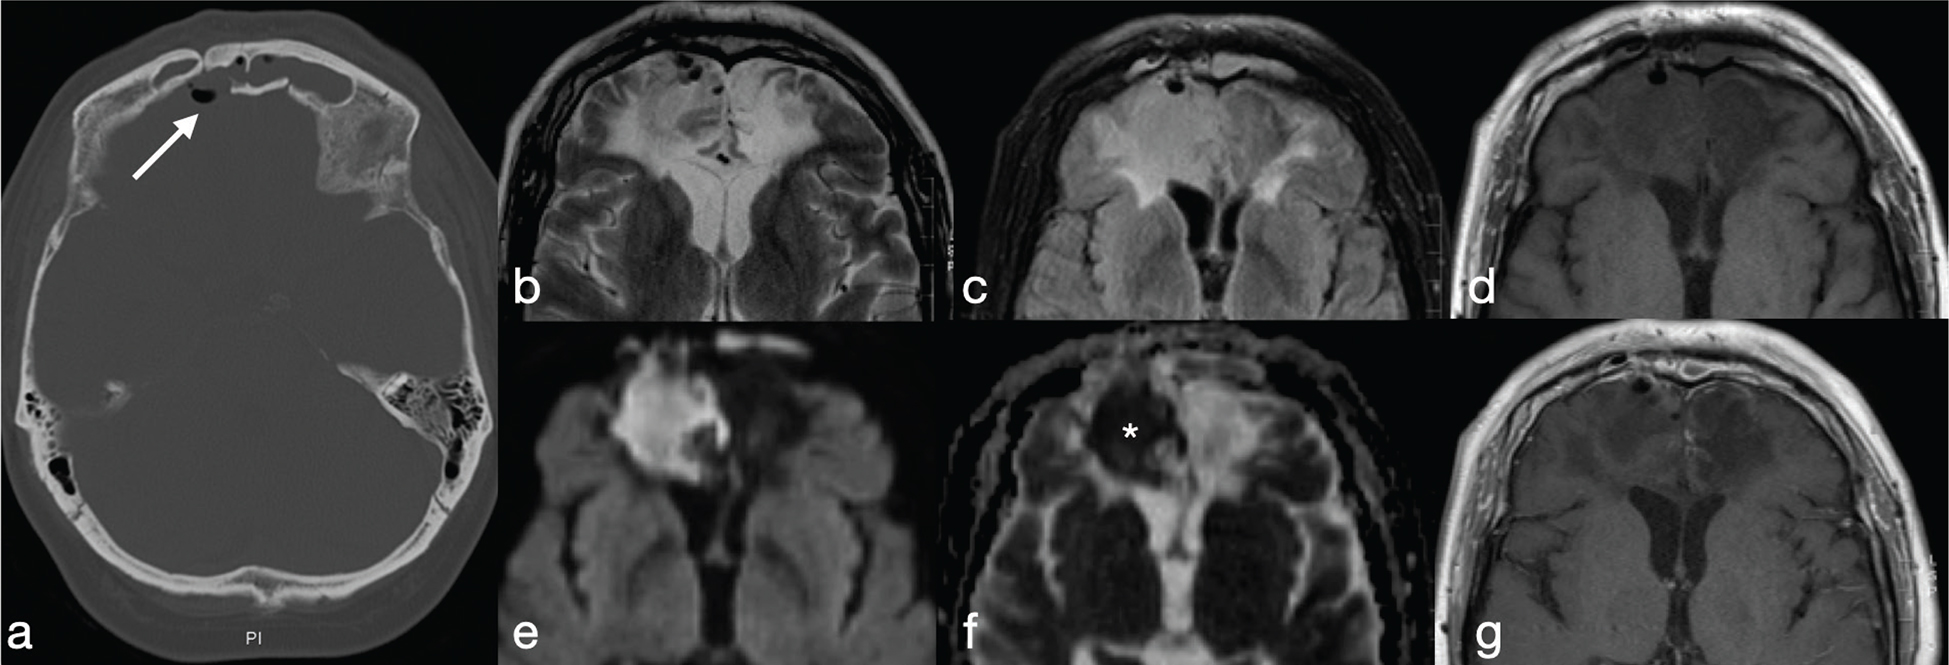

Tuberculous granuloma (tuberculoma) is the most common form of parenchymal CNS tuberculosis. As for pyogenic BA, the cMRI and DWI characteristics depend on the stage of infection: non-caseating, caseating with a solid centre or caseating with a liquid centre (see Table 2). Interestingly, caseating tuberculomas with a liquid centre have an elevated diffusion; indeed, any liquefaction of the central area of necrosis contains a clear fluid, as opposed to pus.7 SWI images may show a complete and regular hypointense peripheral ring.

Tuberculous BA are more similar to pyogenic BA compared to tuberculomas. They usually comprise a multiloculated cavity with central pus, with a thicker wall than a pyogenic BA. It must be distinguished from granuloma with central caseation and liquefaction mimicking pus (Figure 14). However, cMRI does not provide distinction between tubercular and pyogenic BA but lipid peaks without amino acids, on MR spectroscopy, are suggestive of mycobacteria.7

FIG 14. Tuberculoma (a–d) and Tubercular Abscess (e-h). Multiple tuberculomas in both cerebral hemispheres with an hypointense central dot (white arrows in a) within an hyperintense core on T2w are demonstrated. Nodular enhancement on T1+Gd is shown on smaller lesions while the larger one (black arrow in b) shows a thick ring delimitating a cystic core. On DWI and ADC map there is no restricted diffusion (asterisks in c-d). On the contrary, tubercular abscesses located in the quadrigeminal plate show a bright core on T2w, thick peripheral enhancement on T1+Gd (open circle in f) and restricted diffusion on DWI (g) and ADC maps (h).